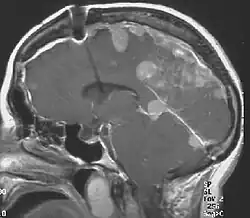

Neurofibromatosis type II (NF2 or NF II; also known as MISME syndrome – multiple inherited schwannomas, meningiomas, and ependymomas) is a genetic condition that may be inherited or may arise spontaneously, and causes benign tumors of the brain, spinal cord, and peripheral nerves. The types of tumors frequently associated with NF2 include vestibular schwannomas, meningiomas, and ependymomas. The main manifestation of the condition is the development of bilateral benign brain tumors in the nerve sheath of the cranial nerve VIII, which is the "auditory-vestibular nerve" that transmits sensory information from the inner ear to the brain. Besides, other benign brain and spinal tumors occur. Symptoms depend on the presence, localisation and growth of the tumor(s). Many people with this condition also experience vision problems.

There are several different surgical techniques for the removal of acoustic neuroma.[19] The choice of approach is determined by size of the tumour, hearing capability, and general clinical condition of the person.

Larger tumors can be treated by either the translabyrinthine approach or the retrosigmoid approach, depending upon the experience of the surgical team. With large tumors, the chance of hearing preservation is small with any approach. When hearing is already poor, the translabyrinthine approach may be used for even small tumors. Small, lateralized tumours in people with NF2 with good hearing should have the middle fossa approach. When the location of the tumour is more medial a retrosigmoid approach may be better.

Radiosurgery is a conservative alternative to cranial base or other intracranial surgery. With conformal radiosurgical techniques, therapeutic radiation focused on the tumour, sparing exposure to surrounding normal tissues. Although radiosurgery can seldom completely destroy a tumor, it can often arrest its growth or reduce its size. While radiation is less immediately damaging than conventional surgery, it incurs a higher risk of subsequent malignant change in the irradiated tissues, and this risk is higher in NF2 than in sporadic (non-NF2) lesions.